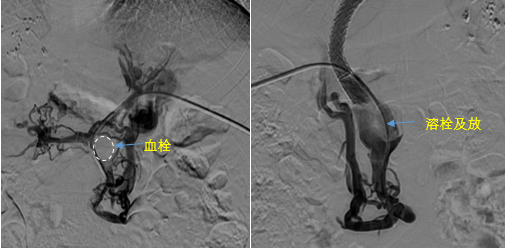

在西安國際醫(yī)學中心醫(yī)院,韓國宏教授對李女士進行了細致的問診及檢查,在CT圖像上仔細的分析,針對患者特殊的病情制定了詳細的治療方案。第一次進入手術(shù)室,在DSA的監(jiān)測下,造影過程中門靜脈血栓的輪廓逐漸顯現(xiàn)出來,見多識廣的醫(yī)生們也大吃一驚,發(fā)現(xiàn)遠端脾靜脈及腸系膜上靜脈也存在大量血栓?;颊叩氖彻芪傅嘴o脈曲張非常嚴重,疏通堵塞的門靜脈已是刻不容緩。

見此情形,韓國宏教授憑借豐富的臨床經(jīng)驗很快調(diào)整了策略,在超聲診療中心的協(xié)助下進行門靜脈右支穿刺,并進行造影,看到目標血管后,韓國宏教授用“明修棧道,暗渡陳倉”的方法,讓來自脾臟和胃腸的血流終于暢通的回流到了肝靜脈。通過血流的沖刷以及抗凝溶栓藥物的作用,幾日后復查造影發(fā)現(xiàn)門靜脈血栓已逐漸變小,不會對回流到肝臟的血流產(chǎn)生大的阻礙作用,門靜脈的壓力顯著減小,患者再次出血的幾率也隨之降低。幾經(jīng)周折,這顆“定時炸彈”終于被拆除,李女士和她的家人多年來心里的石頭也終于落地。